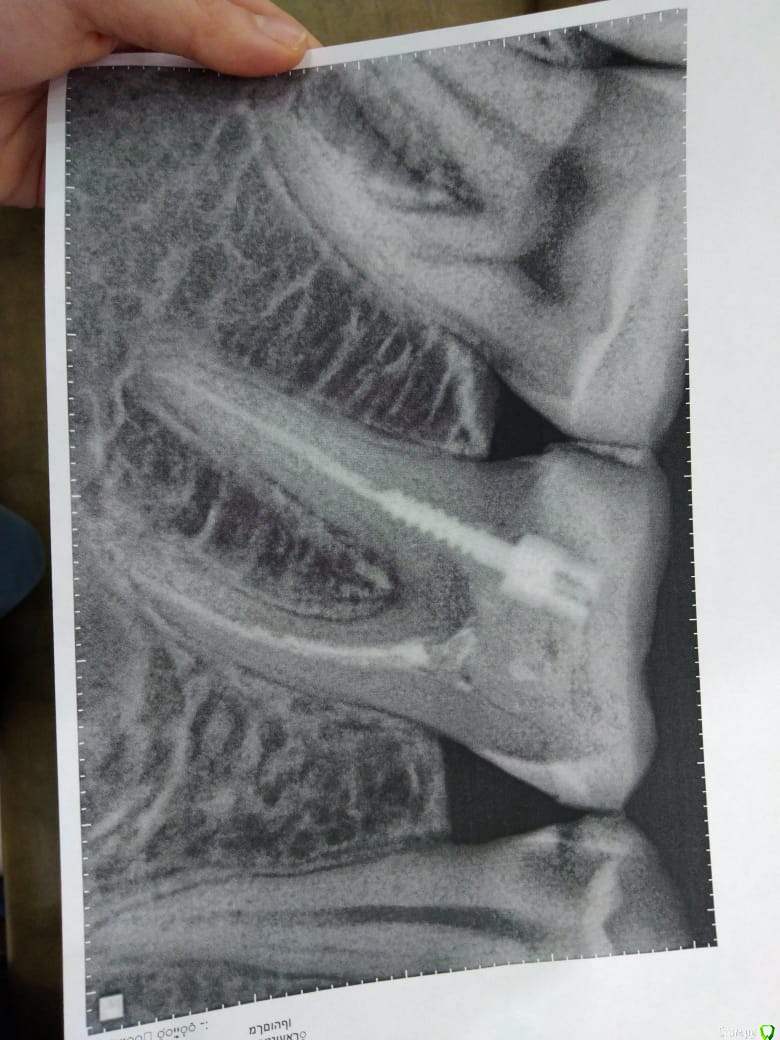

KatrinIvanova Опубликовано 3 марта, 2019 Поделиться Опубликовано 3 марта, 2019 (изменено) Добрый вечер .Обратилась к стоматологу по поводу болей в 46 зубе,нижний моляр справа.Был диагностирован пульпит.Депульпирован,установлен штифт.В течение трёх дней боли не прекращаются,после приема пищи сильная боль ,иррадиирующая в челюсть,ухо,глаза.На улице боль утихает .Боль также беспокоит ночью,утром сегодня отек века .Температуры нет .Снимок прилагаю Изменено 3 марта, 2019 пользователем KatrinIvanova Ссылка на комментарий

St. Опубликовано 3 марта, 2019 Поделиться Опубликовано 3 марта, 2019 Скорее всего есть еще где-то зуб с воспаленным нервом, возможно на верхней челюсти. И обратите внимание на 45 зуб, по снимку там глубокий кариес тоже достаточно близко к нерву уже. утром сегодня отек века С нижними зубами это точно не связано 1 Ссылка на комментарий

dentikl Опубликовано 3 марта, 2019 Поделиться Опубликовано 3 марта, 2019 там похоже еще на предыдущем зубе процесс тоже Ссылка на комментарий